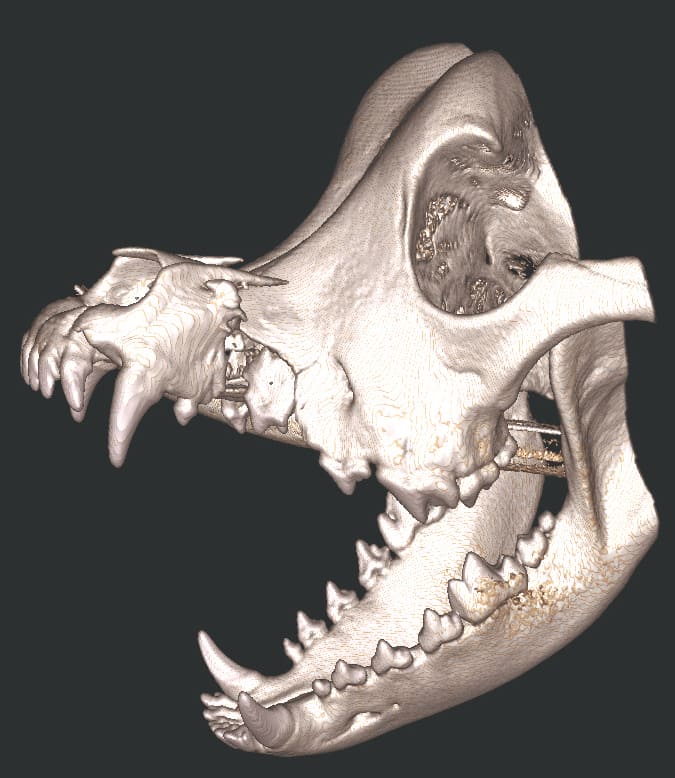

The Center now provides advanced imaging via cone beam CT. Cone beam CT is excellent for visualization of bony structures of the skull, nasal cavity, teeth, and ears. Cone beam CT is especially helpful for diagnosing dental disease and evaluation of jaw fractures. It can also be useful for evaluating the sinuses and tympanic bulla. Cone beam CT can be used in conjunction with nasal biopsy and culture to evaluate nasal discharge whether chronic or acute.

Repair of Maxillofacial Fracture

Pets can be involved in trauma that can cause fractures to their head, teeth, and jaw bones. Correctly repairing these fractures is extremely important for your pet to have normal function of their mouth. If a jaw fracture is allowed to heal in an abnormal position, your pet may have great difficulty chewing and can be in significant pain. Many fractures can be successfully treated with minimally invasive oral procedures, but more complicated cases may require bone plating techniques. The Center offers cone beam CT imaging which provides extremely detailed images of the bones of the head and skull. Advanced imaging with CBCT facilitates selection of the best surgical technique to get your pet back to eating and comfort as soon as possible.